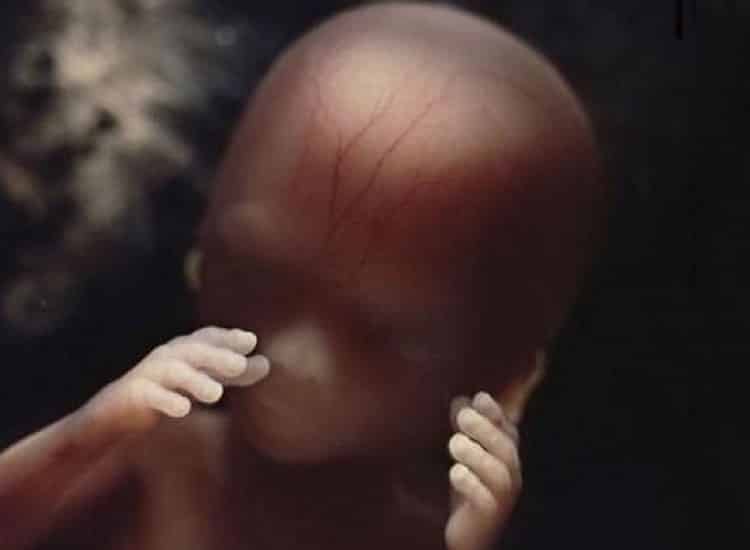

Seu formato mais completo com 16 semanas é este

E a pele é tão transparente e fina que pode-se ver as primeiras veias com sangue